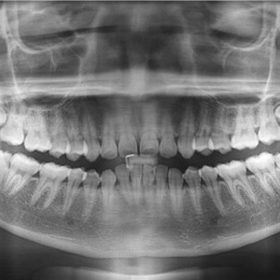

Composite fillings are a modern restoration material made from a mixture of high-quality plastic resin and glass particles. Unlike traditional amalgam (silver) fillings, composite resin can be formulated to match the exact shade and translucency of your natural teeth.

This is the biggest advantage. Silver fillings darken over time, making your teeth look gray or black, especially when you laugh or yawn. Composite fillings blend perfectly with your enamel. whether it is a front tooth or a back molar, the filling remains your little secret.

2. Conservative Treatment (Less Drilling)

Metal fillings require dentists to remove a significant amount of healthy tooth structure to create a “pocket” to hold the material in place. Composite fillings, on the other hand, chemically bond directly to the tooth surface. This means we can preserve more of your natural tooth structure, keeping the tooth stronger in the long run.